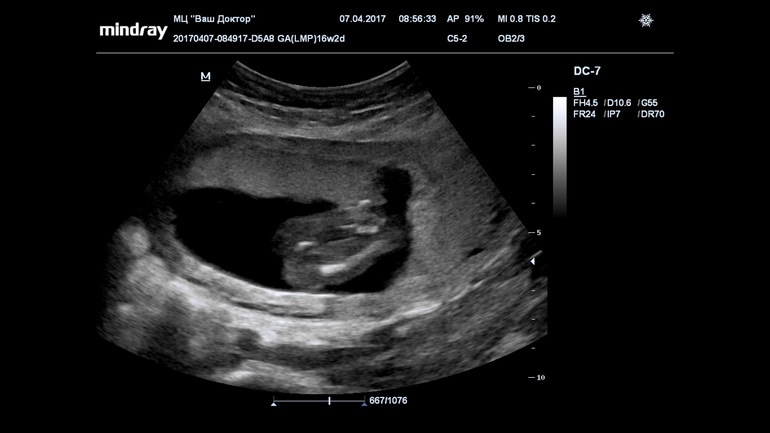

18-19 недель-сынка!)))